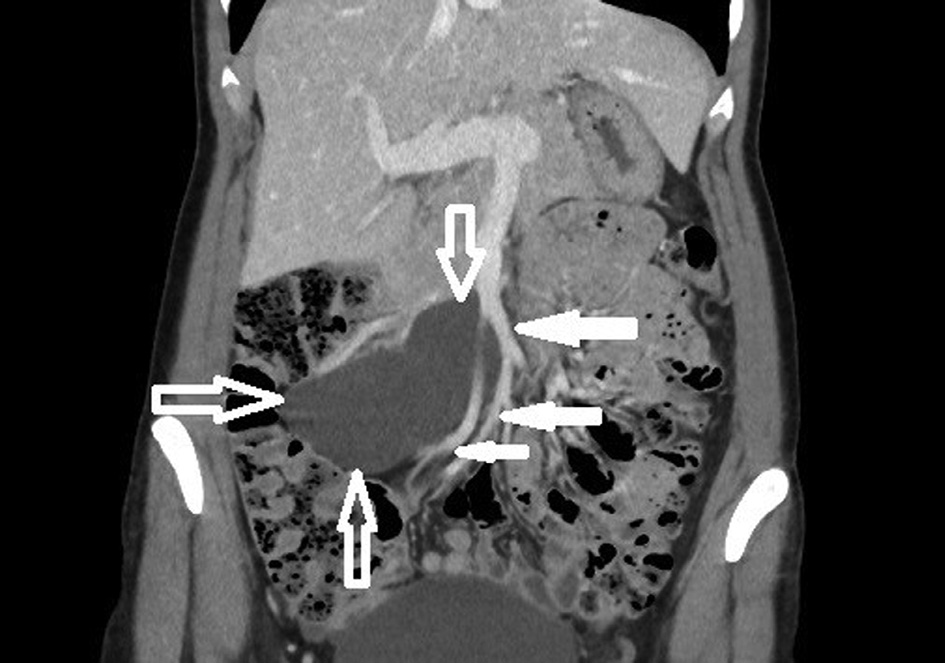

The 42-year-old woman sought medical attention for periodically occurring moderately severe pain in the lower abdomen. Intermittent lower abdominal pain occurred 2 years ago for the first time. She was investigated in the emergency department a few times. The pain gradually increased over the time. Physical examination revealed that the patient was well and no physical changes were identified. CT scan revealed a clearly defined, hypodensic, cystic, without clear solid components mass, about 11 cm × 10 cm × 6,5 cm, ventrally reaching the right side of abdomen wall, dorsally contacting abdominal aorta, inferior vena cava and right common iliac artery, caudally lying on the ileocolic artery and vein (Fig. 1 and Fig. 2). The mass extended from pancreatic head and superior mesenteric vein near ileum to right iliac area along the ileocolic artery and vein. Lymphangioma of the ileum mesentery was suspected. Also, an atypical anatomy of the celiac trunk was detected.